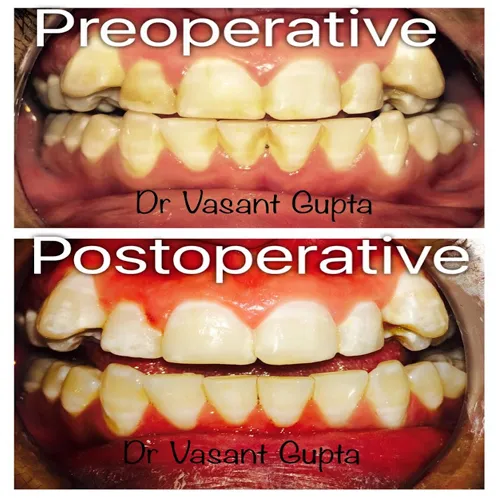

DR. VASANT GUPTA

B.D.S., M.D.S.

ENDODONTIST

Regn No. : HN-6165 A